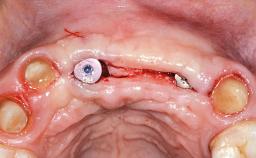

Replacement of Four Incisors with a Fixed Partial Denture on Two Narrow-Neck Implants after Implant Failure

| Jaw | Maxilla |

| Area | Anterior |

| # of Teeth | 4 |

| # of Implants | 2 |

| Type of Implants | One-Piece|Reduced-Diameter |